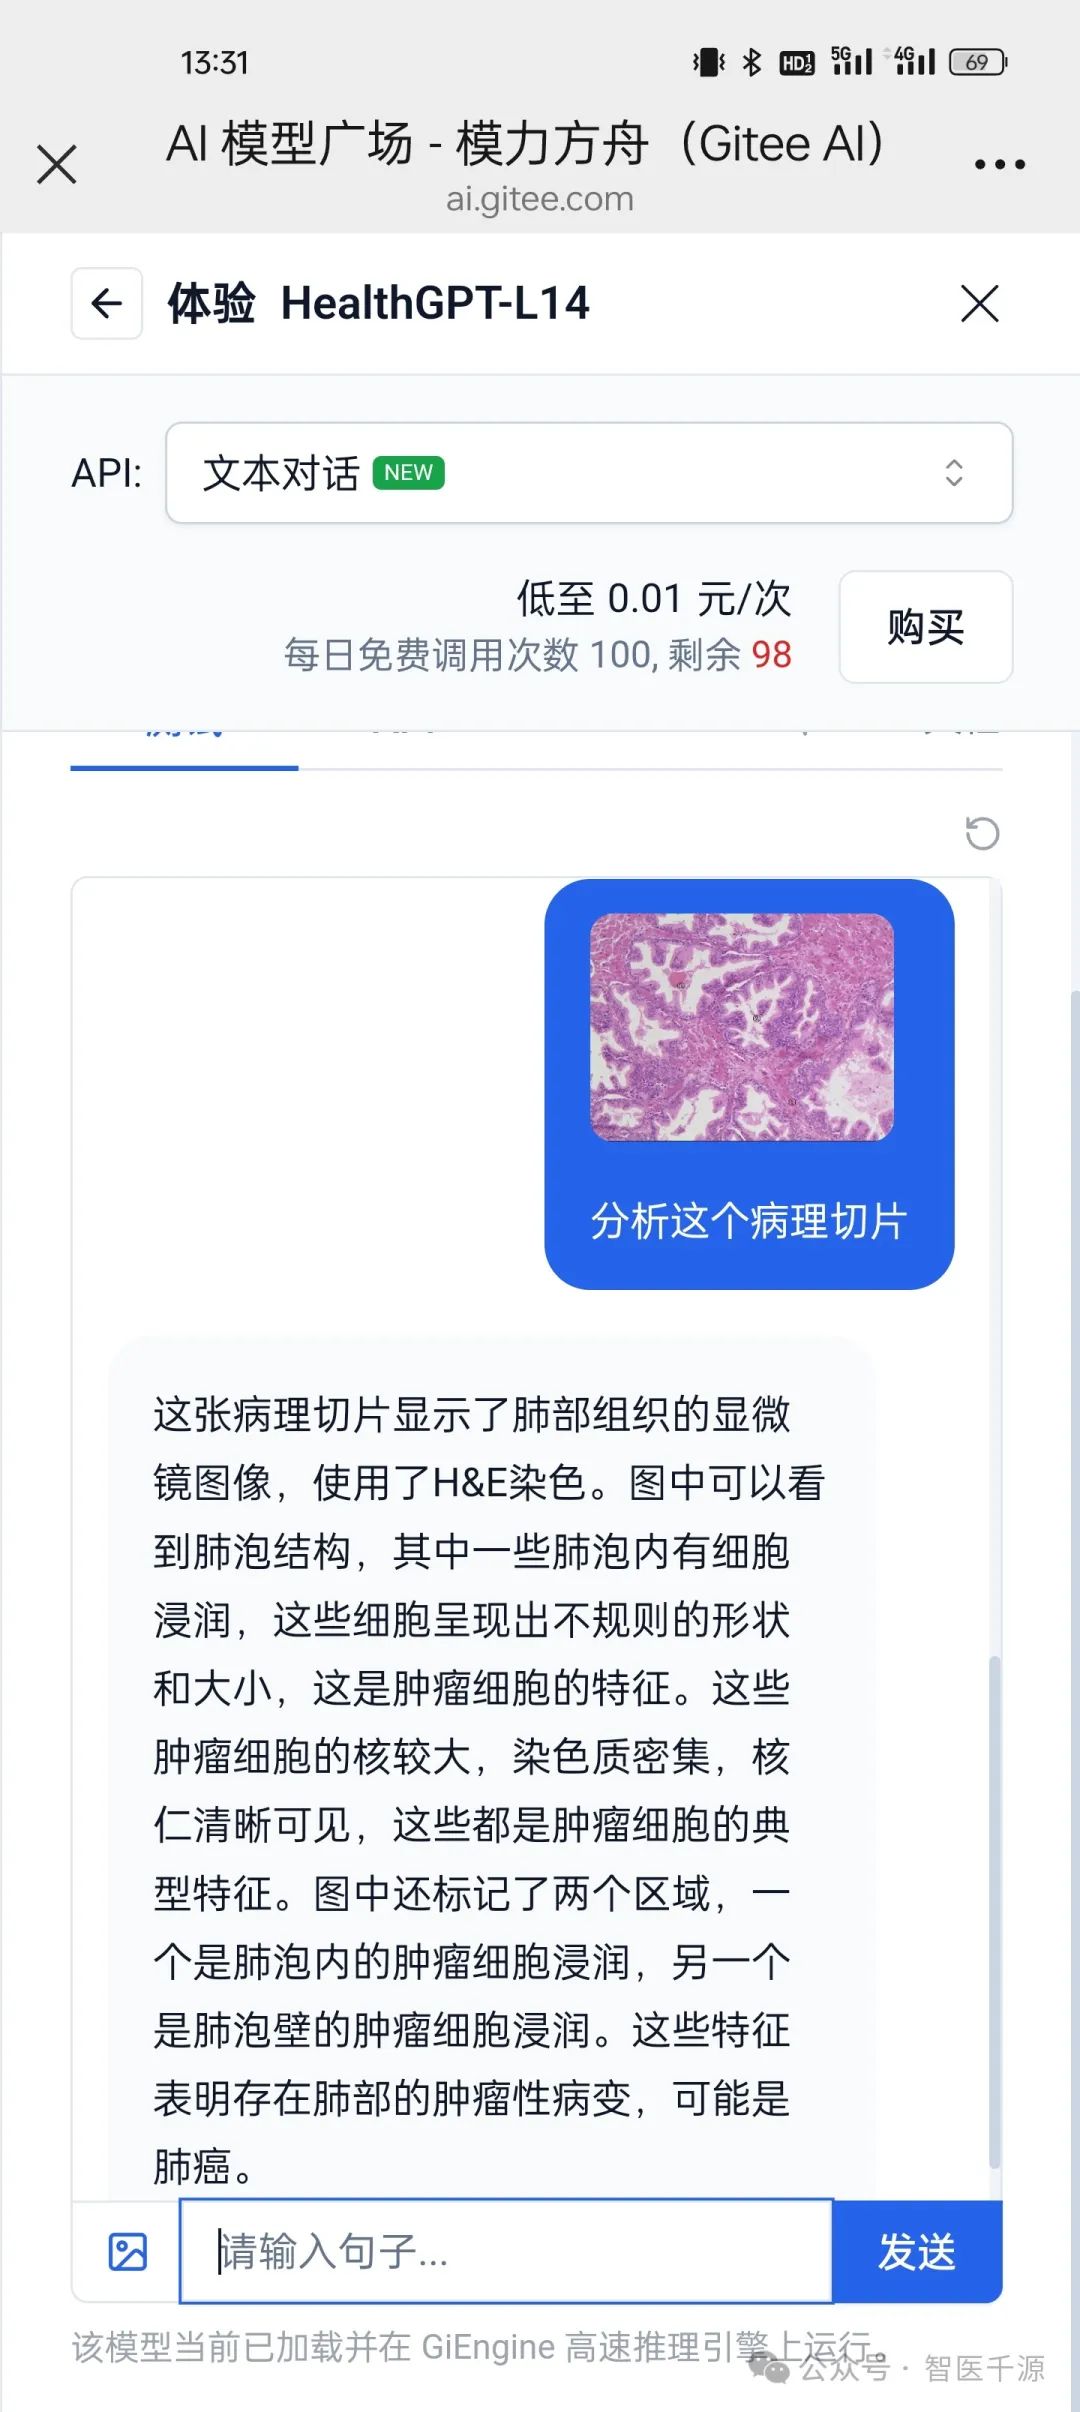

前段时间,我在业余时间折腾了一下AI病理识别,然后我的好朋友红薯CTO就在模力方舟上整了个专门做医疗视觉识别的多模态大模型HealthGPT,由浙江大学、新加坡国立大学等机构联合研发,是一个专注于医疗领域的多模态大语言模型(Med-LVLM),旨在通过统一框架整合视觉理解和生成能力。

给出的结果如下:

这张病理切片显示了肺部组织的显微镜图像,使用了H&E染色。图中可以看到肺泡结构,其中一些肺泡内有细胞浸润,这些细胞呈现出不规则的形状和大小,这是肿瘤细胞的特征。这些肿瘤细胞的核较大,染色质密集,核仁清晰可见,这些都是肿瘤细胞的典型特征。图中还标记了两个区域,一个是肺泡内的肿瘤细胞浸润,另一个是肺泡壁的肿瘤细胞浸润。这些特征表明存在肺部的肿瘤性病变,可能是肺癌。